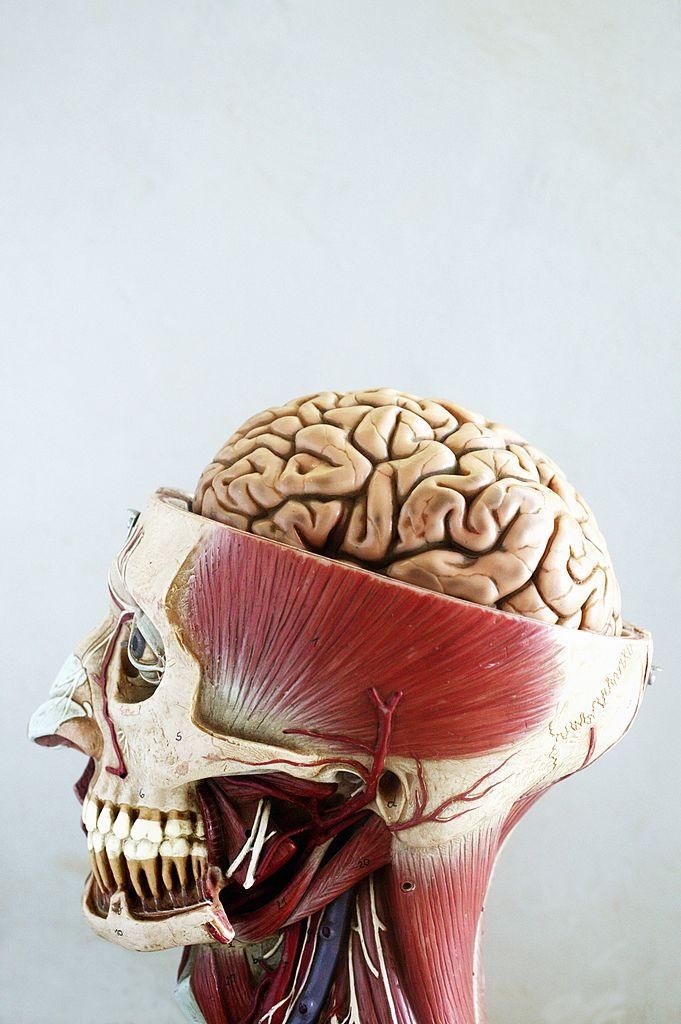

Il cervello è l’organo più complesso e meraviglioso del nostro corpo. Tuttavia, è una struttura misteriosa ed è avvolta da numerosi equivoci e bufale.